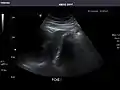

Spleen: Normal in size.

Spleen